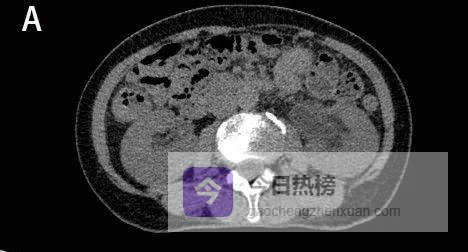

图1A

CT平扫示左肾及左侧输尿管扩张积水。